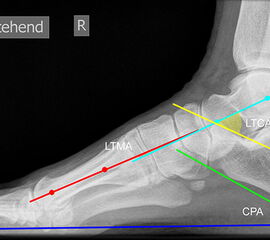

Beurteilung von Fehlstellungen des Mittel- und Rückfußes

Zur Vollansicht und zum Lesen der Bildbeschreibung bitte die Bilder anklicken.

Achsen auf der lateralen Aufnahme

Die Grundlinie (blau) ist definiert durch den tiefsten Punkt der Sesambeine und den tiefsten Punkt des Kalkaneus.

CPA (Calcaneal pitch angle): Der Kalkaneus Inklinationswinkel liegt zwischen der Grundlinie (blau) und der plantaren Begrenzung des Kalkaneus (grün) (Norm 20,8 ± 4,1° 11, 15-39° (Zwipp 2014)).

LTCA (Lateral talocalcaneal angle): Der laterale talokalkaneare Winkel liegt wird gebildet aus der Talusachse (türkis) und einer Verbindungslinie zwischen dem Oberrand des Proc. ant. Calcanei und der dorsalen Begrenzung des Kalkaneus (gelb). (Norm: 33° Range 25-45°) 1213).

LTMA (Lateral talometatarsal angle, Syn. Meary’s angle): Der laterale talometatarsale Winkel wird gebildet aus der Achse des Os metatarsale I (rot) und der Achse des Talus (türkis). (Norm: 7,1 ± 10,8 11).